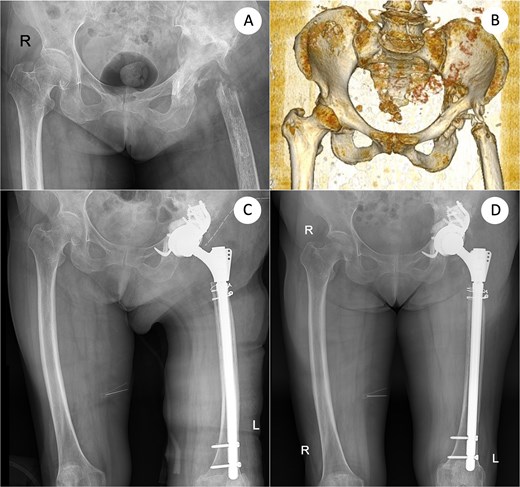

A 73-year-old woman presented with severe bone loss of the left proximal femur and extensive acetabular deficiency with pelvic discontinuity (Fig. 1). Initial treatment in 2017 for a displaced femoral neck fracture was bipolar hemiarthroplasty (Fig. 2A and B). After a new injury in 2019, an acetabular fracture with intrapelvic migration of the bipolar head occurred (Fig. 2C), leading to conversion to total hip arthroplasty with a revision acetabular component supported by a cup–cage (“trap”) construct (Fig. 2D). In 2023, PJI developed with loosening of both components; the acetabular component was explanted and a central pedicled vastus lateralis flap transposed to manage dead space (Fig. 2E and F). In May 2024, the femoral component was removed (Fig. 3A). CT confirmed mixed cavitary–segmental acetabular defects and marked metaphyseal loss of the proximal femur (Fig. 3B). After normalization of inflammatory markers and soft-tissue healing, salvage re-revision THA was performed. Acetabular reconstruction used a 52-mm porous shell–cage; two 45-mm tongues engaged host ilium and ischium, and cavitary defects were filled with antibiotic-loaded polymethylmethacrylate. Fixation comprised three intra-shell screws, four rim screws, and two tongue screws (Fig. 3C). On the femoral side, 2 cm of compromised proximal femur was resected to bleeding bone; the canal was reamed to 15 mm for circumferential endosteal contact. A modular tapered, fluted stem (14 × 260 mm) achieved distal fixation, supplemented by two distal interlocking screws; prophylactic cerclage mitigated iatrogenic fracture risk (Fig. 3C). Postoperatively, weight bearing advanced as tolerated. Serial AP pelvis radiographs showed a stable cup–cage without migration or progressive radiolucency and a well-seated stem without subsidence. At 10 months there were no complications, no infection or dislocation, and the patient ambulated with a cane; radiographs remained stable (Fig. 2D).

Definitive salvage re-revision THA: Defect assessment after femoral explant (AP and 3D-CT) and final reconstruction. (A) AP pelvis after removal of the femoral component showing severe acetabular and proximal femoral bone defects. (B) Three-dimensional computed-tomography (3D-CT) reconstruction corresponding to (A), confirming mixed cavitary–segmental acetabular defects. (C) Immediate postoperative AP radiograph after salvage re-revision total hip arthroplasty using a cup–cage acetabular reconstruction and a 260-mm modular tapered femoral stem secured with two distal interlocking screws. (D) AP X-ray taken 10 months after re-revision. AP, anteroposterior; 3D-CT, three-dimensional computed tomography; THA, total hip arthroplasty.